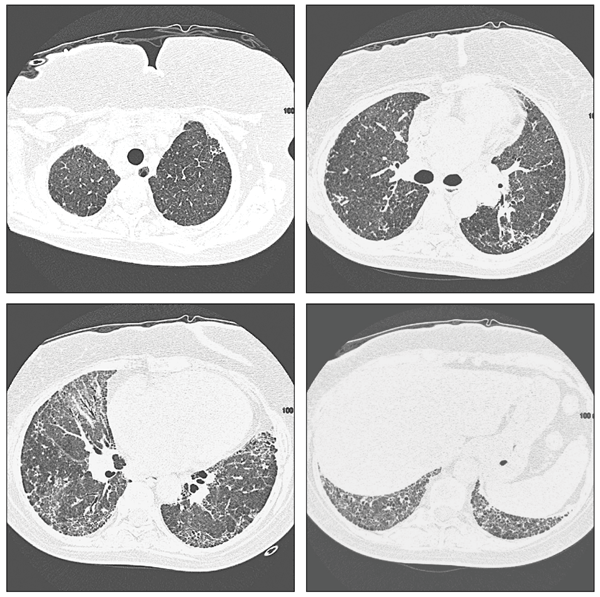

Patients with organizing pneumonia may present with a flu-like illness with fever, cough, weight loss, and progressive dyspnea. Chest radiographs demonstrate patchy areas of consolidation, ground-glass and nodular opacities, and bronchial wall thickening and dilation (Figure 4).16 Lung biopsy demonstrates preserved lung architecture with distinct intraluminal buds of granulation tissue (Figure 5).

Figure 4 – Multifocal airspace opacities can be seen on these chest radiographs from a patient with drug-induced organizing pneumonia.